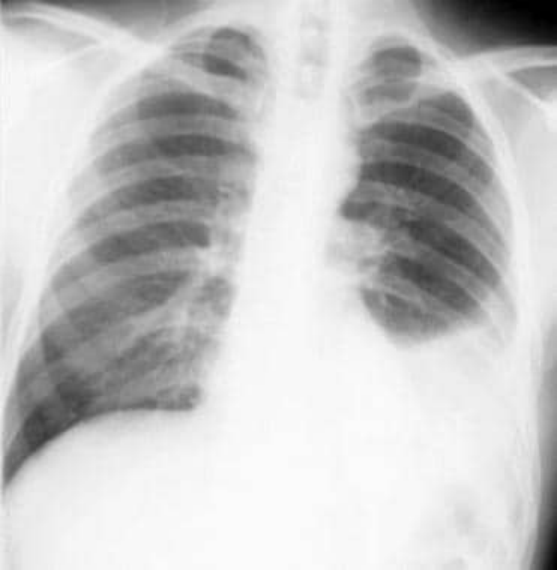

非小细胞肺癌。继发于左主支气管的支气管癌继发的完全左肺塌陷。